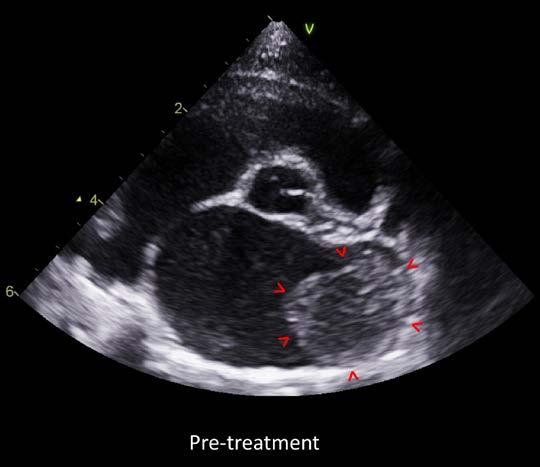

The echocardiogram confirmed that Dusty had ventricular hypertrophy with severe left and moderate right atrial enlargement (LA 2.6cm, LA:Ao 2.8) There was no evidence of left ventricular outflow tract obstruction using Doppler. The scan also confirmed the mass effect noted was in fact likely to be a large thrombus, which appeared adherent, within the left auricle/atrium (1.3 x 1.8 cm in size). This was deemed to have arisen secondary to atrial remodeling/stretch, blood flow stasis, and endothelial injury. This thrombus presented a high risk for Dusty developing severe thromboembolism or experiencing sudden cardiac death.

Due to the presence of a large left atrial thrombus, aggressive antithrombotic therapy was recommended. The aim was to achieve slow dissolution of the thrombus without causing dislodgement or thromboembolism. However, there was a significant risk of thromboembolism with or without therapy and a guarded prognosis was provided to the owner.

Figure 1. Echocardiogram images of the right parasternal short-axis view of the left atrium both pre and post treatment with dual antithrombotic medications rivaroxaban and clopidogrel. Red arrows outline the left atrial thrombus.

Dusty was re-evaluated by Damon 6 months later, to recheck the previously diagnosed HCM and left atrial thrombus. The echocardiographic findings were consistent with the previous diagnosis of severe hypertrophic cardiomyopathy. There was persistent markedly severe left and right atrial enlargement (LA 2.6cm, LA:Ao 2.6), and Dusty remained at high risk for CHF. However much to our surprise, following antithrombotic therapy, there was echocardiographic evidence of dissolution of the thrombus. This indicated an excellent response to therapy and the risk of thromboembolism was now much lower.